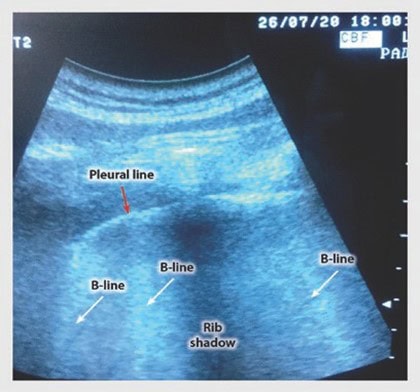

- Eco: líneas B no cuantifican el edema pulmonar, incremento de agua pulmonar extravascular. Efusiones pleurales, NT, consolidaciones pulmonares, función diafragmática (POCUS)